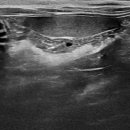

남양주 다산동물병원 24시 고양이건강검진 후기 신장검사 원동물의료센터 경기 남양주시 다산중앙로 15... 24시 동물병원에서 고양이 건강검진을 하고온 후기를 소개해드릴게요. ⏰ 영업시간: 24시 주차 ⭕ 병원...

이후에 병원에서 전화가 와서 아이를 데릴러 오면 되더라고요 특히 담당쌤이 검사결과를 보면서 건강상태와 주의 할점? 등등 자세히 설명해 주셨어요 남양주 다산동물병원 24시 고양이건강검진 베이직 검사...

중증, 만성질환 관리 시스템이 잘 구축되어 있어 장기적으로 꾸준히 관리받기 좋은 병원이라는 느낌을 받았어요. 남양주 다산동물병원 24시 고양이건강검진 원동물의료센터는 단순 검진을 넘어 아이의 삶...